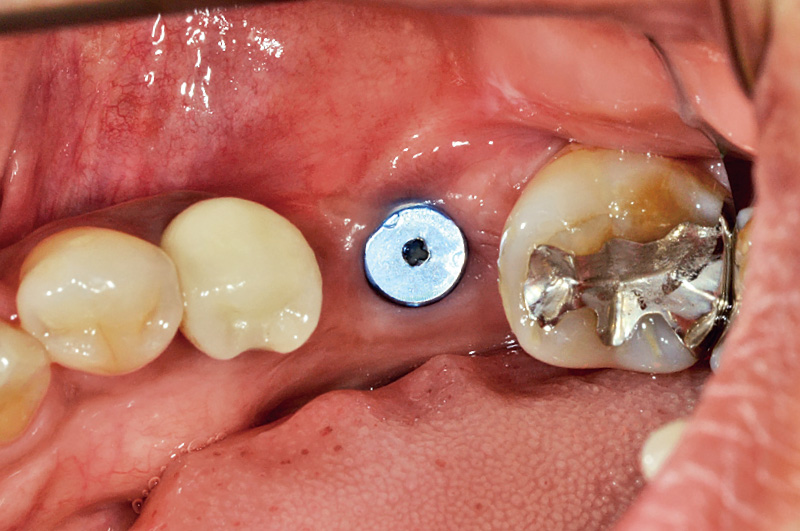

![[写真] 2次手術前](/academic/dentalmagazine/wp-content/uploads/sites/2/2025/11/195-10_photo02.jpg)

図2 2次手術前

SPIインプラントの埋入後、ヒーリングキャップが装着されている写真を示す。術後6か月が経過しており、2次手術の前の状態である。#24, 25にはCERECを用いて行った。即日処置のシリカ系セラミックス製修復・補綴装置が接着してある。 -